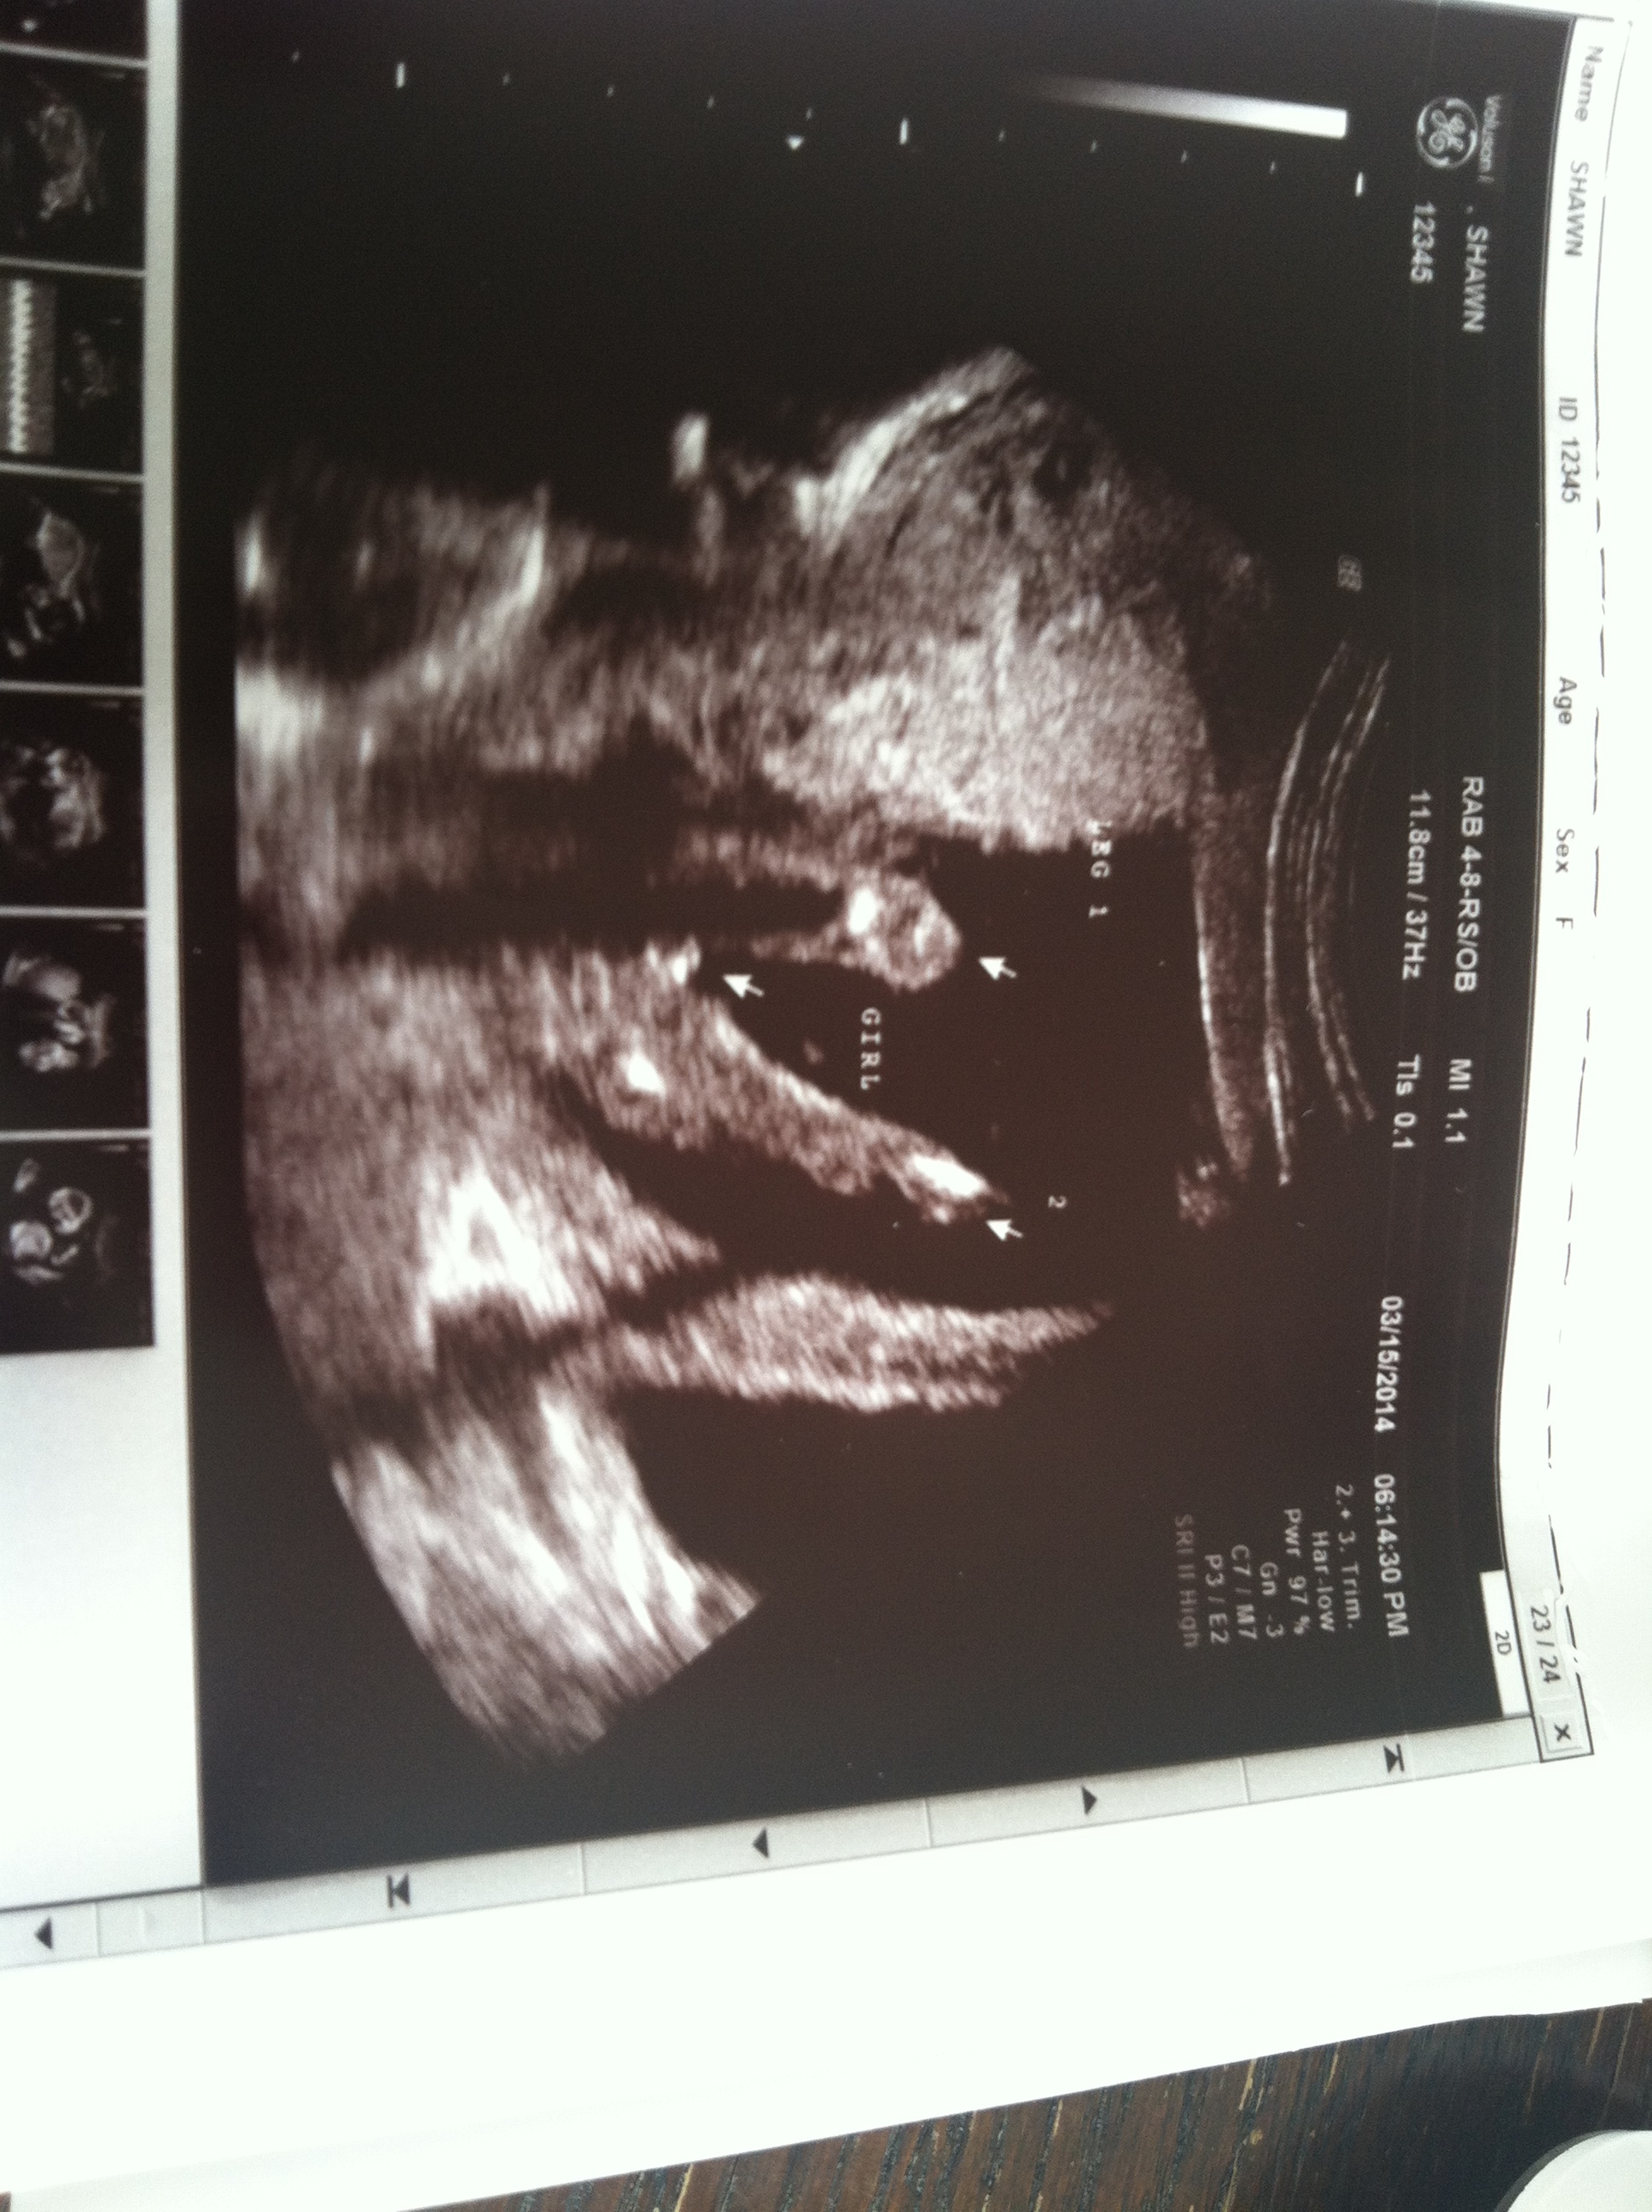

Hi Everyone...thanks in advance for your input. I have 3 boys and pregnant with baby #4. Had an ultrasound at 16w and after a long time of trying to get this modest baby to turn around-u/s tech believes that we have baby girl. I've only ever seen baby boy ultrasounds so just wanted to get some opinions bc I know 16 weeks could still be early!

Attachment 17661